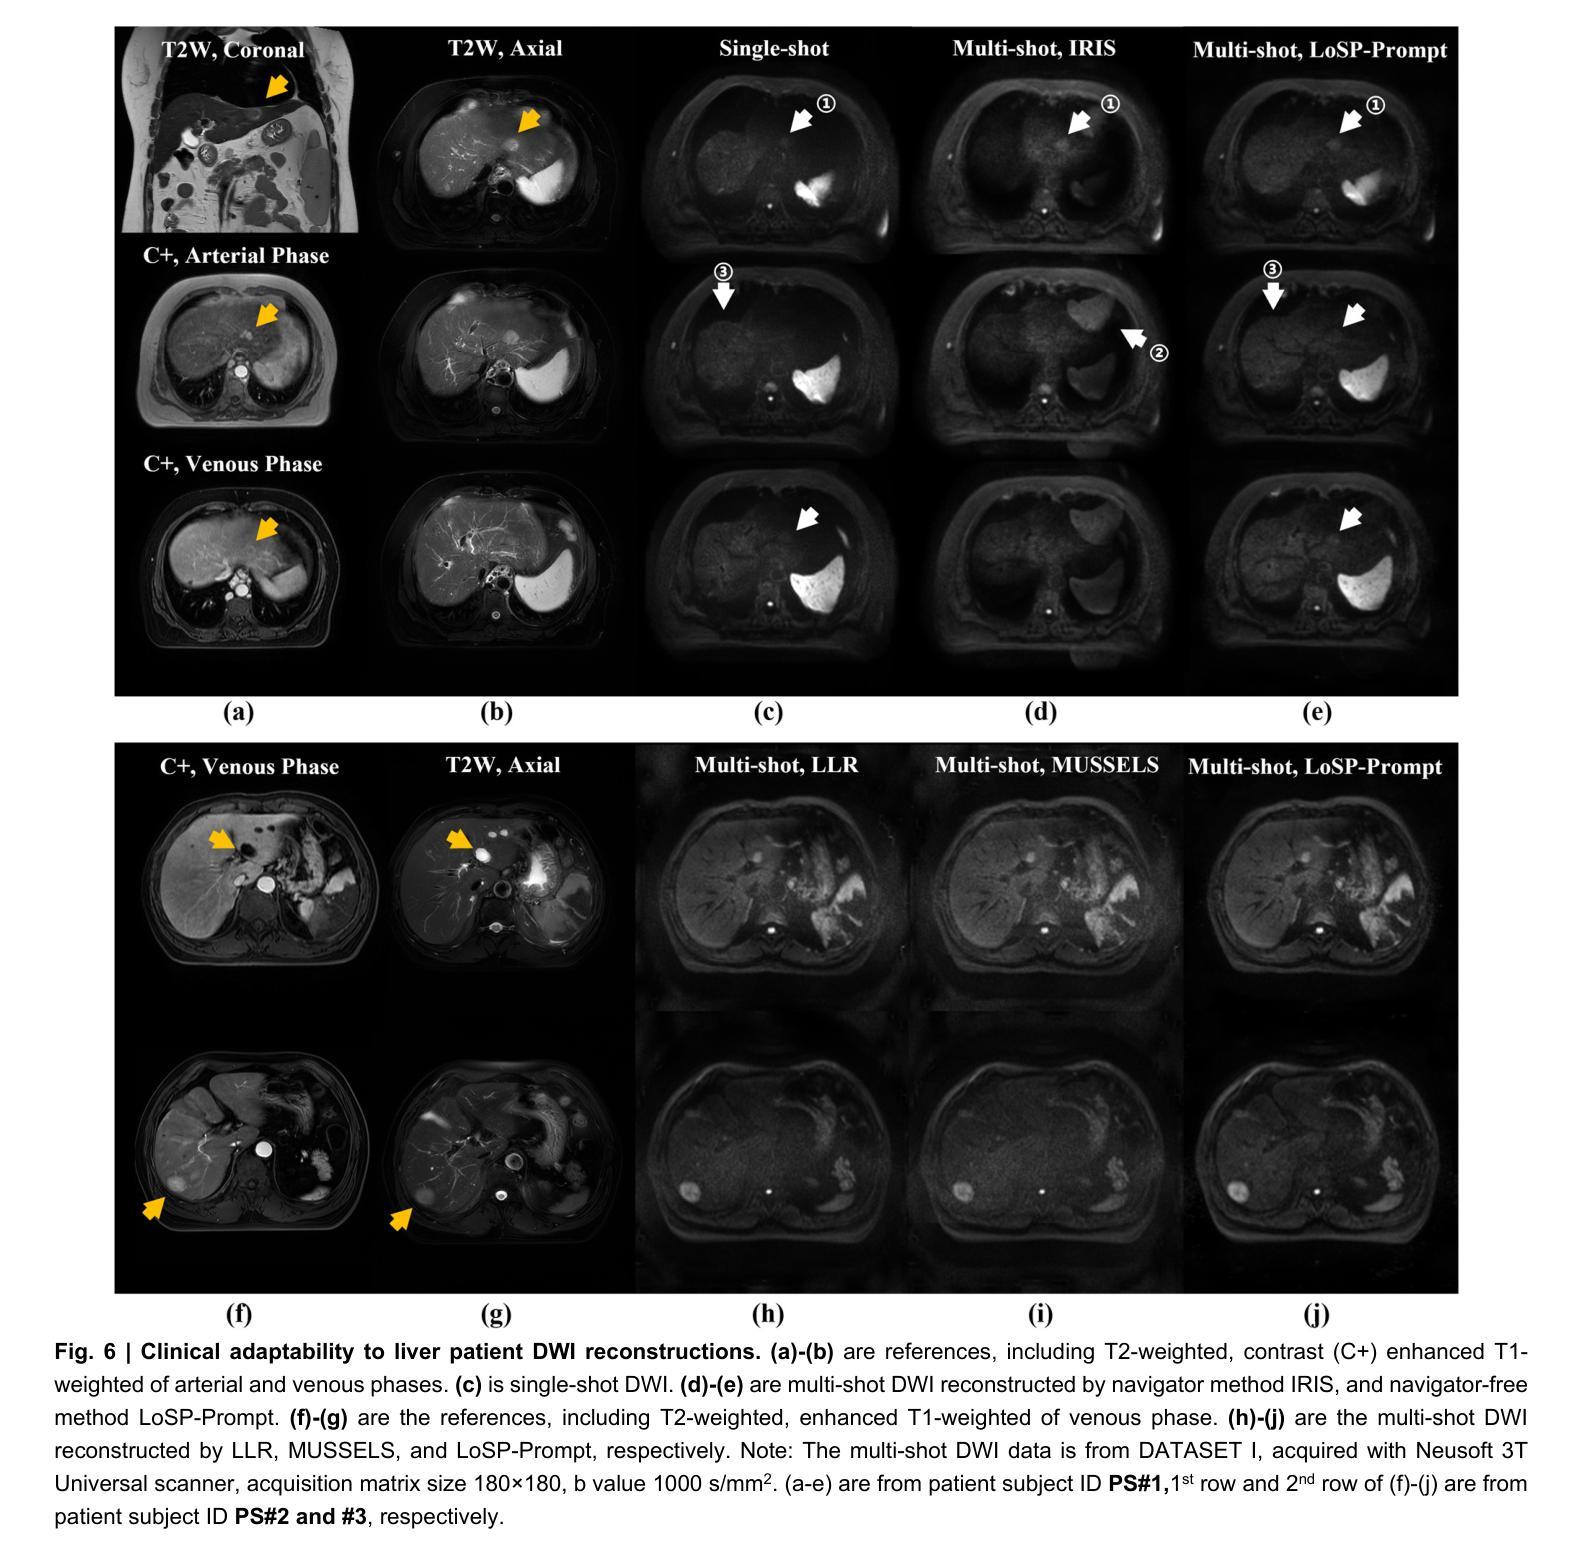

Clinical adoption of multi-shot diffusion-weighted magnetic resonance imaging (multi-shot DWI) for body-wide tumor diagnostics is limited by severe motion-induced phase artifacts from respiration, peristalsis, and so on, compounded by multi-organ, multi-slice, multi-direction and multi-b-value complexities. Here, we introduce a reconstruction framework, LoSP-Prompt, that overcomes these challenges through physics-informed modeling and synthetic-data-driven prompt learning. We model inter-shot phase variations as a high-order Locally Smooth Phase (LoSP), integrated into a low-rank Hankel matrix reconstruction. Crucially, the algorithm’s rank parameter is automatically set via prompt learning trained exclusively on synthetic abdominal DWI data emulating physiological motion. Validated across 10,000+ clinical images (43 subjects, 4 scanner models, 5 centers), LoSP-Prompt: (1) Achieved twice the spatial resolution of clinical single-shot DWI, enhancing liver lesion conspicuity; (2) Generalized to seven diverse anatomical regions (liver, kidney, sacroiliac, pelvis, knee, spinal cord, brain) with a single model; (3) Outperformed state-of-the-art methods in image quality, artifact suppression, and noise reduction (11 radiologists’ evaluations on a 5-point scale, $p<0.05$), achieving 4-5 points (excellent) on kidney DWI, 4 points (good to excellent) on liver, sacroiliac and spinal cord DWI, and 3-4 points (good) on knee and tumor brain. The approach eliminates navigator signals and realistic data supervision, providing an interpretable, robust solution for high-resolution multi-organ multi-shot DWI. Its scanner-agnostic performance signifies transformative potential for precision oncology.

在临床采用多回扩散加权磁共振成像(multi-shot DWI)进行全身肿瘤诊断时,受到呼吸、蠕动等引起的严重运动相位伪影的限制,再加上多器官、多切片、多方向和多b值的复杂性。在这里,我们引入了一种重建框架,名为LoSP-Prompt,它通过物理信息建模和合成数据驱动提示学习来克服这些挑战。我们将不同射击之间的相位变化建模为高阶局部平滑相位(LoSP),并将其集成到低秩Hankel矩阵重建中。关键的是,该算法的秩参数是通过仅使用模拟生理运动的合成腹部DWI数据进行提示学习来自动设置的。在超过10,000张临床图像(43名受试者,4种扫描仪型号,5个中心)的验证中,LoSP-Prompt:(1)实现了临床单发DWI两倍的空间分辨率,提高了肝脏病变的清晰度;(2)使用单一模型推广到七个不同的解剖区域(肝脏、肾脏、骨盆、膝盖、脊髓、大脑);(3)在图像质量、伪影抑制和降噪方面优于最新方法(11名放射科医生在五点量表上进行评估,p<0.05),在肾脏DWI上获得4-5分(优秀),肝脏、骨盆和脊髓DWI上获得4分(良好至优秀),膝盖和肿瘤大脑获得3-4分(良好)。该方法消除了导航信号和真实数据监督,提供了一种可解释、稳健的解决方案,用于高分辨率多器官多回DWI。其扫描仪无关的性能表明对精准肿瘤学具有变革潜力。

Summary

在医学图像领域中,针对体部肿瘤的诊断采用了多站式扩散加权磁共振成像(multi-shot DWI),但由于呼吸、蠕动等引起的严重运动引起的相位伪影限制了其临床应用。为解决此问题,本文提出了一种重建框架LoSP-Prompt,通过物理信息建模和合成数据驱动的提示学习来克服这些挑战。该算法实现了临床单站式DWI的两倍空间分辨率,提高了肝脏病变的辨识度,并在多个解剖区域具有广泛应用性。此外,其在图像质量、伪影抑制和降噪方面均优于现有技术,并在肾脏DWI上取得了卓越表现。此方法无需导航信号和真实数据监督,提供了一种可解释、稳健的高分辨率多站式DWI解决方案,对精确肿瘤学具有变革潜力。

Key Takeaways

1. 多站式扩散加权磁共振成像(multi-shot DWI)在临床应用中受到限制,主要由于运动引起的相位伪影。

2. 提出了一种重建框架LoSP-Prompt,通过物理信息建模和合成数据驱动的提示学习来解决挑战。

3. LoSP-Prompt实现了两倍于临床单站式DWI的空间分辨率,提高了肝脏病变的辨识度。

4. 该方法可在多个解剖区域广泛应用,包括肝脏、肾脏、骨盆、膝盖、脊髓和大脑。

5. LoSP-Prompt在图像质量、伪影抑制和降噪方面表现出卓越性能,优于现有技术。

6. 该方法无需导航信号和真实数据监督,提供了可解释性和稳健性。